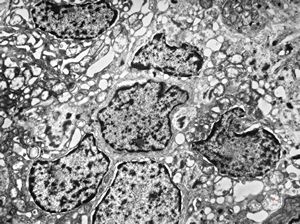

M,1y. | plexus papilloma